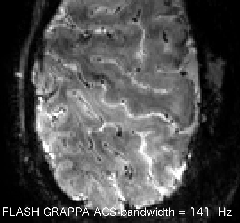

tSNR maps for various ACS schemes: FLASH is better than FLEET. FLEET is often better than single shot. And “segmented” is usually the worst.

FLASH-GRAPPA

FLASH GRAPPA can have a huge impact on signal tSNR. Here an example of segmented vs. FLASH GRAPPA.

In FLASH GRAPPA, the reference lines are acquired without most of the biases of EPI-based reference data. E.g. no distortions, no delays between lines etc.